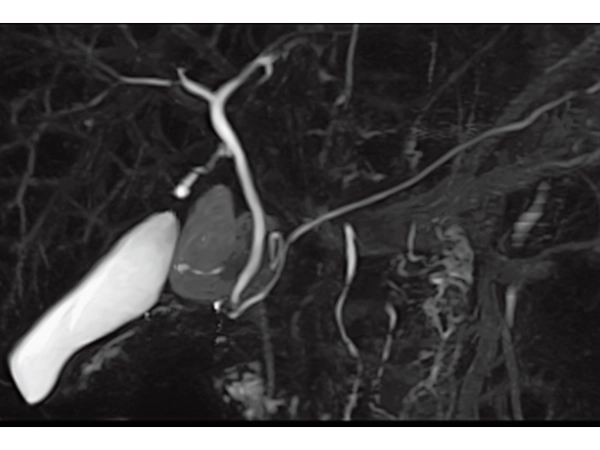

3DisoFSE MRCP (MIP)

Respiratory gating, 2:50